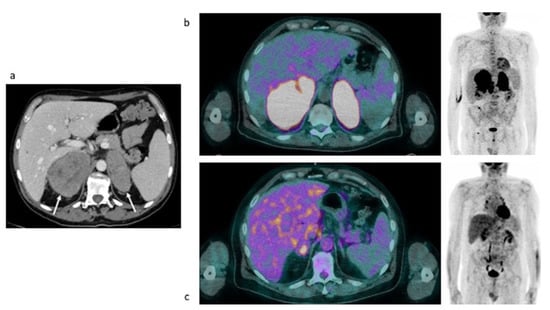

3.2.2. Restaging: Case #2